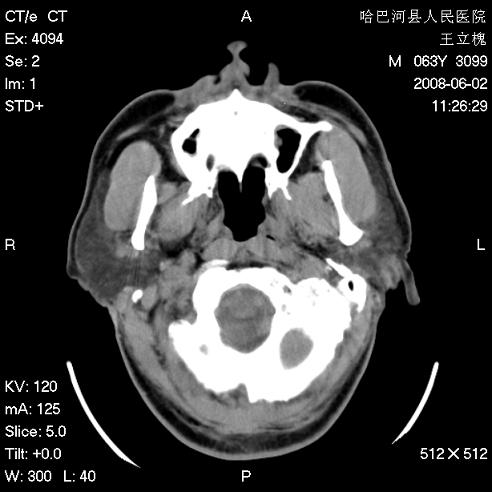

标题: CT13803:反复性鼻塞、流涕一年余 [打印本页]

标题: CT13803:反复性鼻塞、流涕一年余

副鼻窦炎,右上额窦积脓。左眼肌锥内见致密影,视神經受压

1.全组副鼻窦炎2.双侧上颌窦积液

1)全副鼻窦炎(左侧上颌窦黏膜下囊肿或息肉)。2)左眼眶肌锥内不规则小结节状软组织密度影;考虑为小血管瘤可能。建议行ct增强扫描检查。

全组副鼻窦炎,左侧肌锥内不规则形软组织肿块影,与眼外肌密度相当,左侧视神经受压,肿块与视神经及眼外肌分界清晰,眼外肌无增粗,眶壁无破坏,球后脂肪间隙不模糊,考虑良性改变,小血管瘤或神经源性肿瘤可能,建议增强扫描。

谢谢,增强扫描做了,眶内病灶与海绵窦同步明显强化,血管瘤